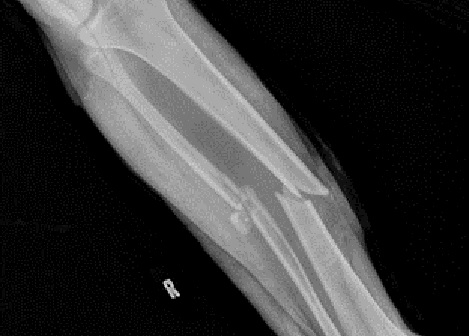

Fig8. - Open tibia fracture.

Fig8. - Treated with a monolateral external fixator.